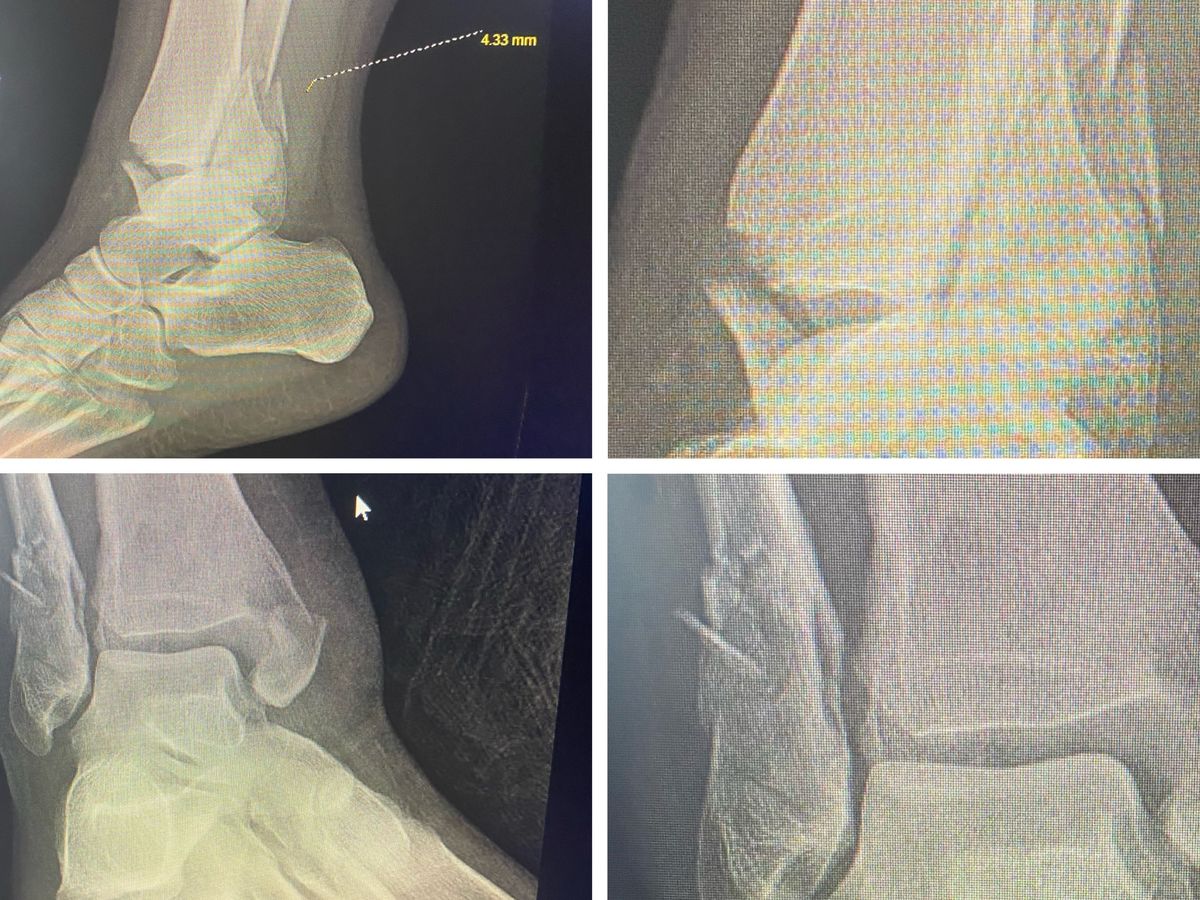

Hello, my name is Kesha a lot of people know me as Dymyneyz. On February 19th while exercising with my husband on skates, I hit a rock and lost balance breaking all 3 major bones that holds the foot in tact, which resulted in me needing surgery to get plates and screws put in all the way around. That resulted in me having to take an unpaid leave from work. I work for Elkhart community schools and I’m also a hairstylist/braider. My household took a major financial loss from this. Right now EVERYTHING is falling on my husband. Bills, food, caring for our special needs daughter Shay, as well as taking care of me, but not enough funds to handle it all by himself. We went from 4 incomes to only 1 so if you could find it in your heart to help us in this situation it would be greatly appreciated. I was always told a closed mouth don’t get fed, and I know if I don’t ask or do something to help, then my duty as a wife and mother wouldn’t be met. I want to thank any and everyone in advance that decides to help out. Although this was one of the hardest things to do, I have to do something instead of doing nothing at all.